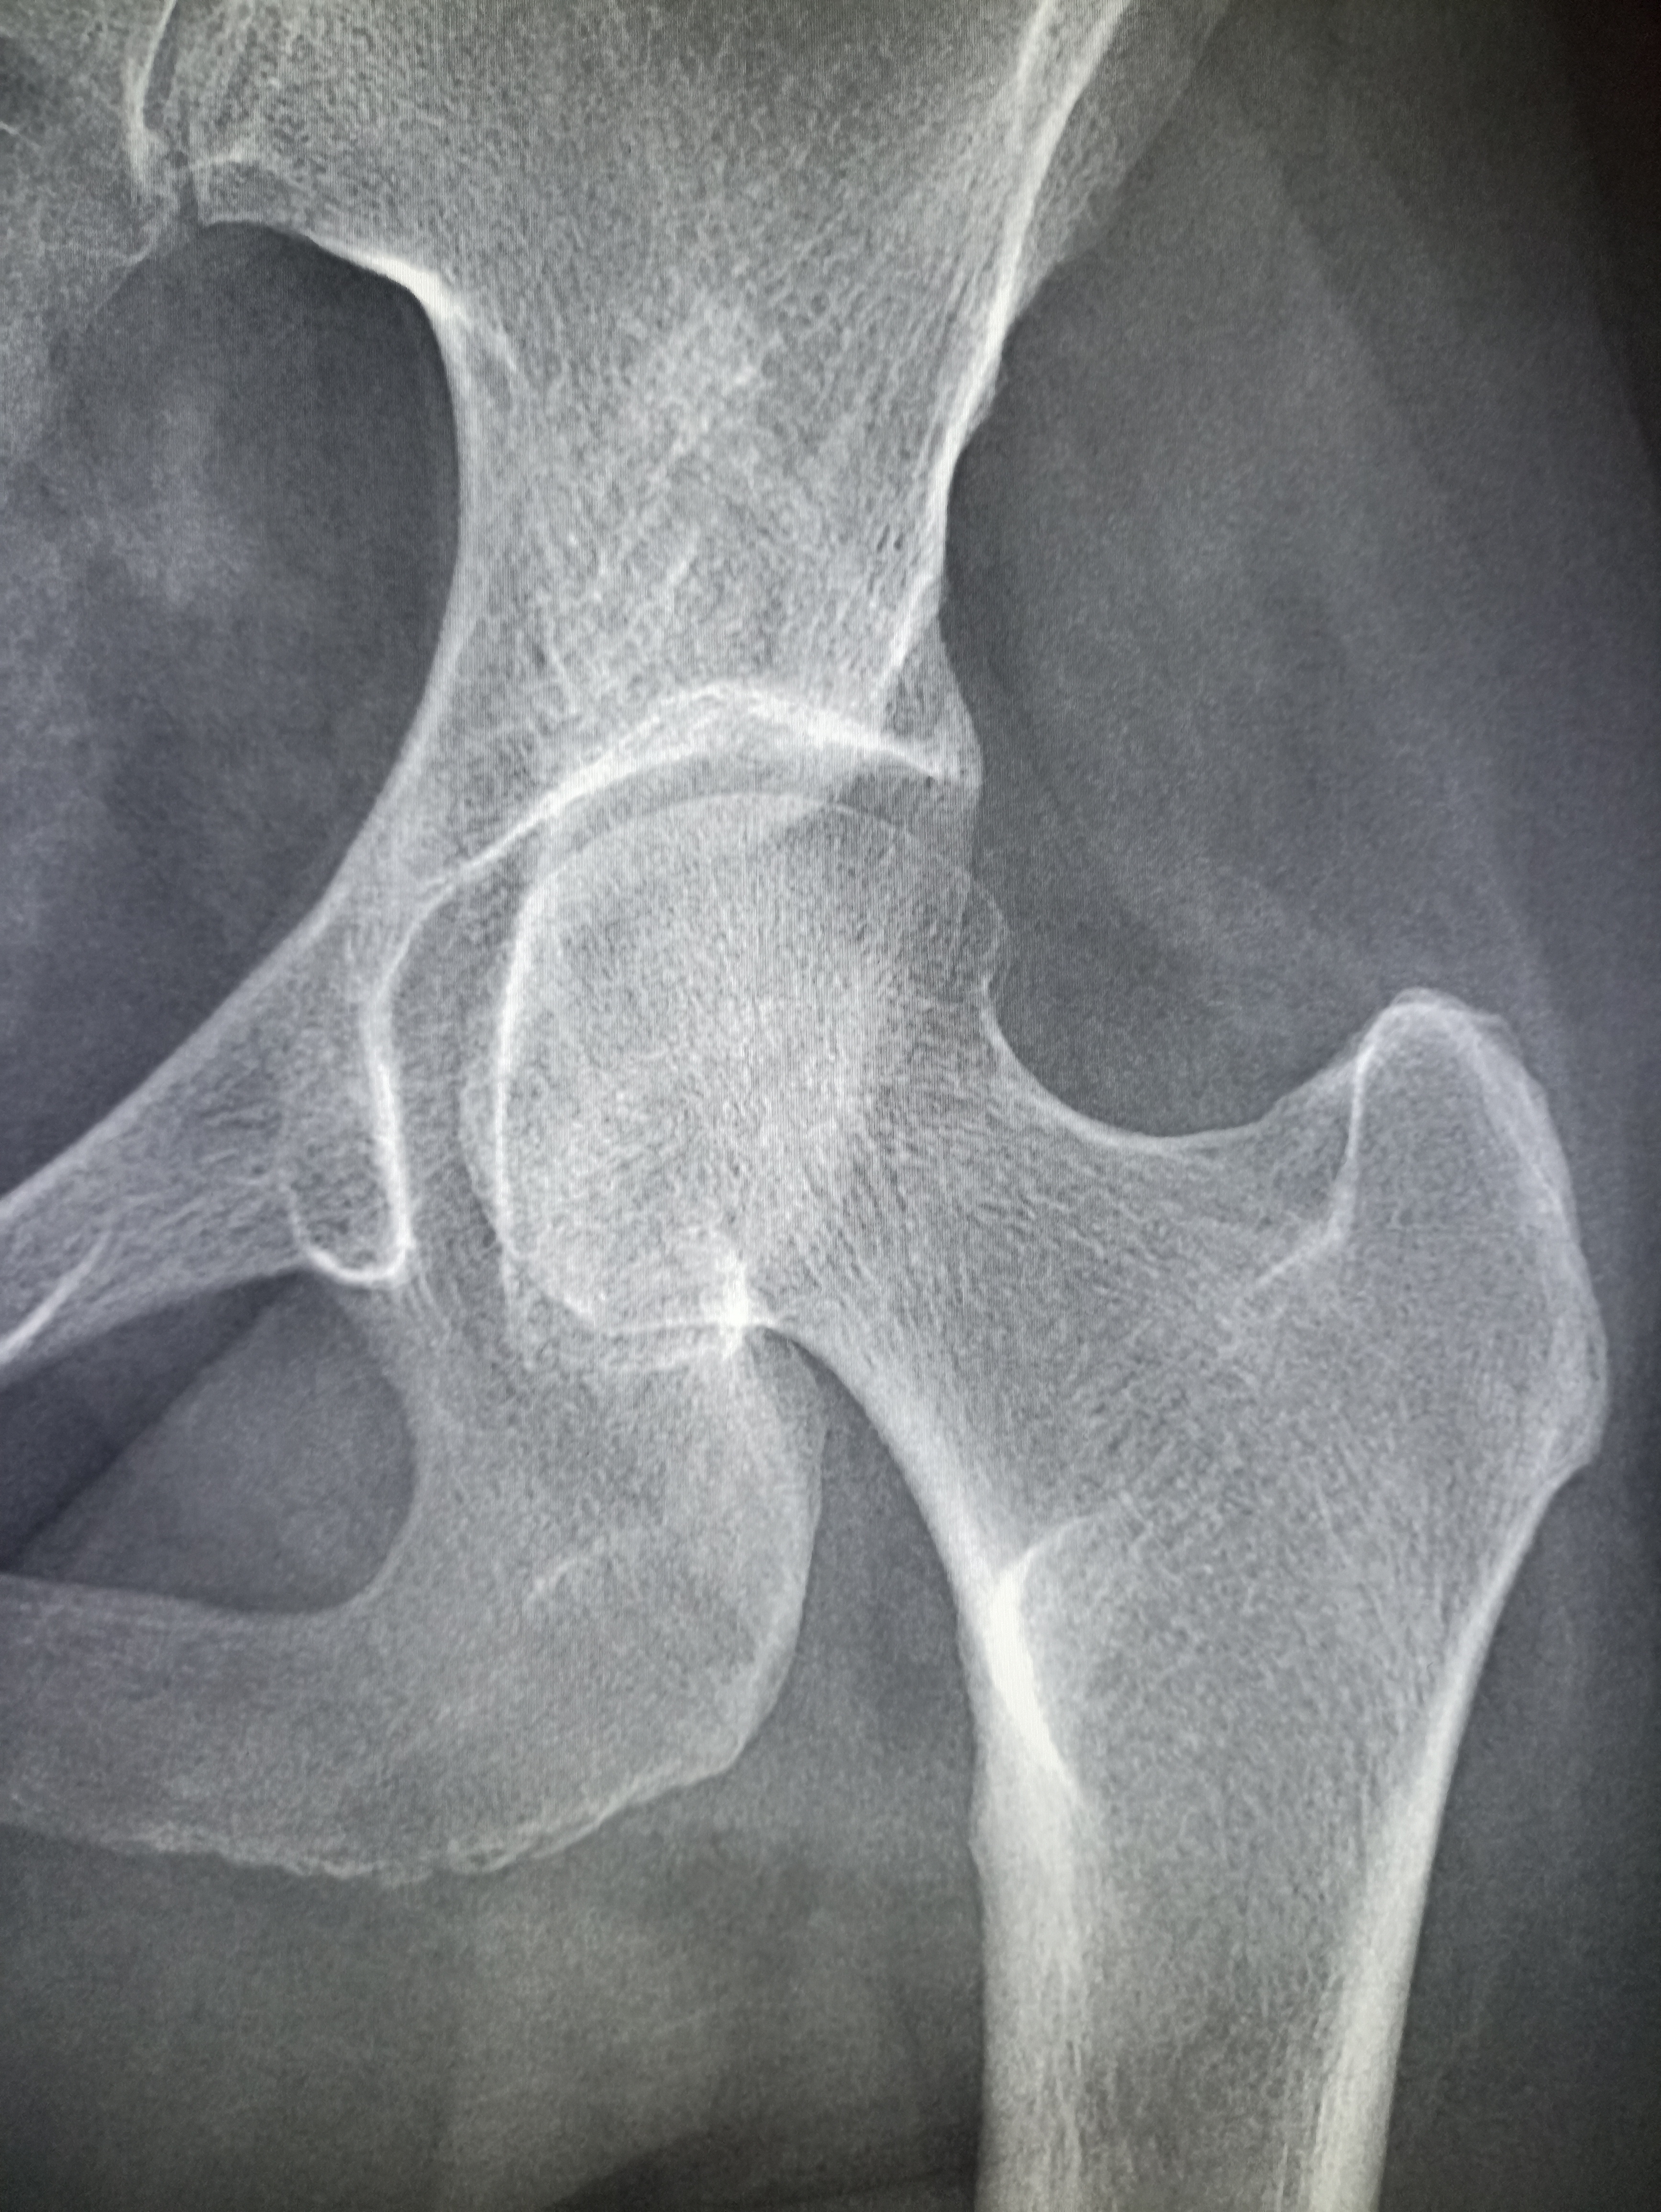

IMG20251013130959.jpg

Чо тут у нас?

IMG20251008112937.jpg

Где пиздецома?

>>325600080

Коксоартроз

>>325599324

тут очевидный гиперостеохондроз